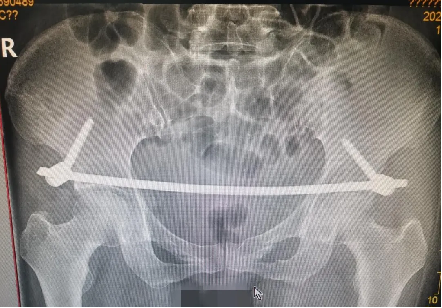

患者因外伤致骨盆前环骨折,患者难以忍耐长期卧床及疼痛,要求行手术治疗以期早日自主翻身坐立活动。

案例三

创伤性骨盆骨折致尿道断裂患者,膀胱造瘘术后,需稳定骨折端避免二次伤害。

骨盆前环微创经皮内固定技术(INFIX技术)固定结合了内固定和外固定的优点,扬长避短,针对此类患者,有效避免了术后深部感染,又避免了使用外固定的手术并发症,让患者在最佳治疗时机获得了骨盆环的稳定,并能早期开始功能锻炼,最大程度上降低了因伤致残的机率。